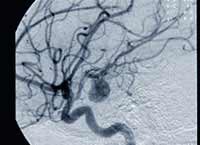

Aneurismas intracranianos também ocorrem em vários membros de famílias suscetíveis. Aneurisma é a dilatação irregular de uma artéria que pode se romper ou trombosar. O rompimento pode levar a uma hemorragia do tipo subaracnóidea. Quando isso ocorre, cerca de 40% dos pacientes morrem e a maior parte dos demais experimenta problemas sérios causados por danos ao cérebro promovidos pelo rápido sangramento.